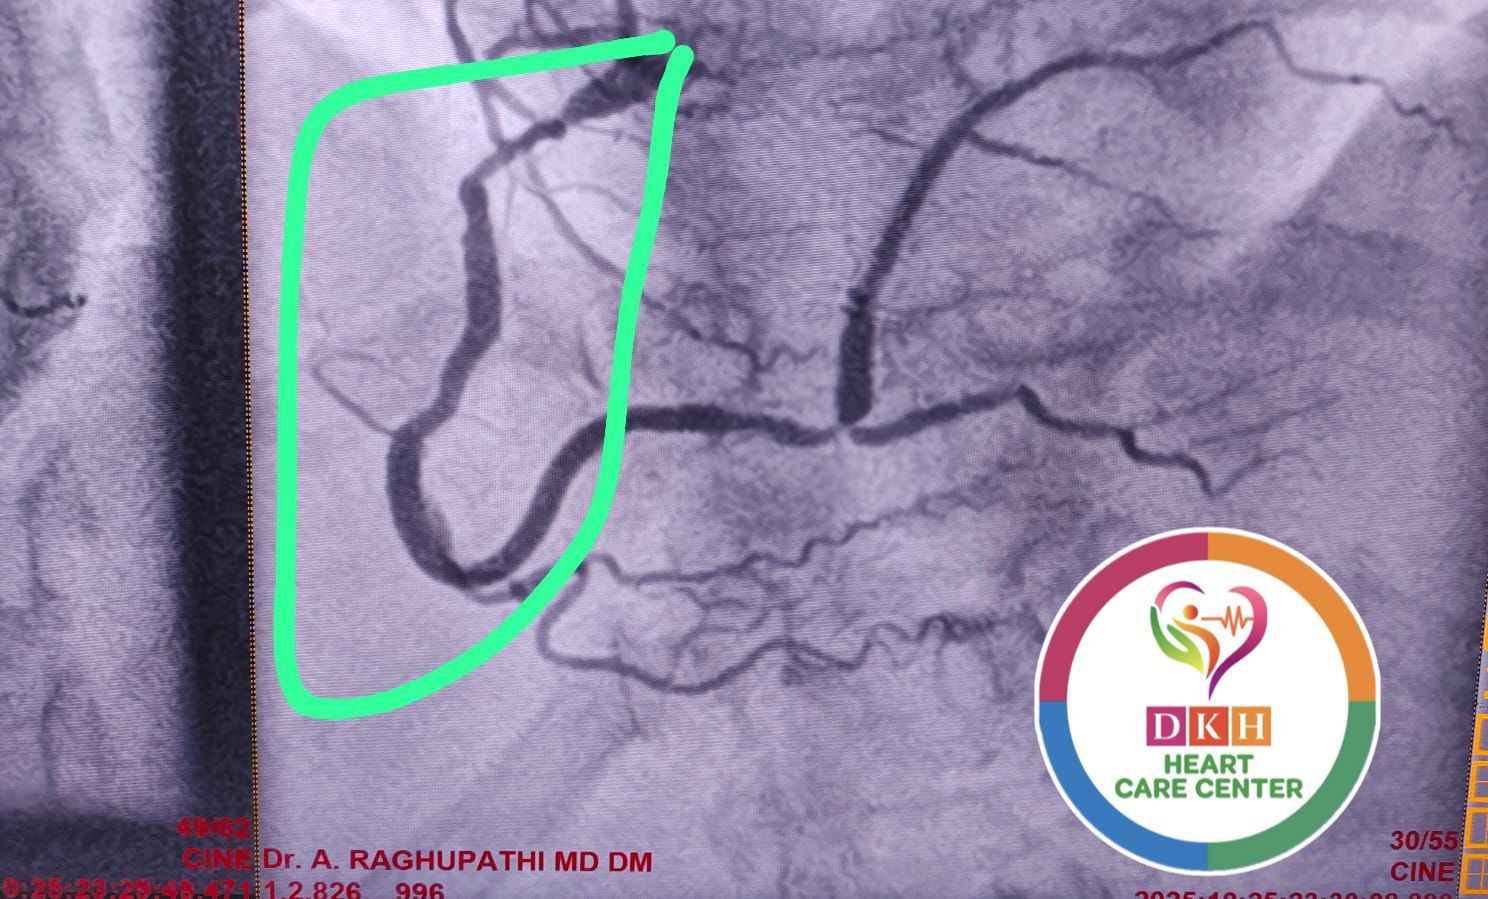

Deepa Kannan Hospital Heart Care Center & Cath Lab stands as a beacon of excellence in cardiovascular medicine. With state-of-the-art catheterization laboratory facilities and a team of renowned cardiac specialists, we are committed to providing comprehensive heart care services that combine cutting-edge technology with personalized patient care.

State-of-the-art cardiac catheterization laboratory with advanced imaging technology